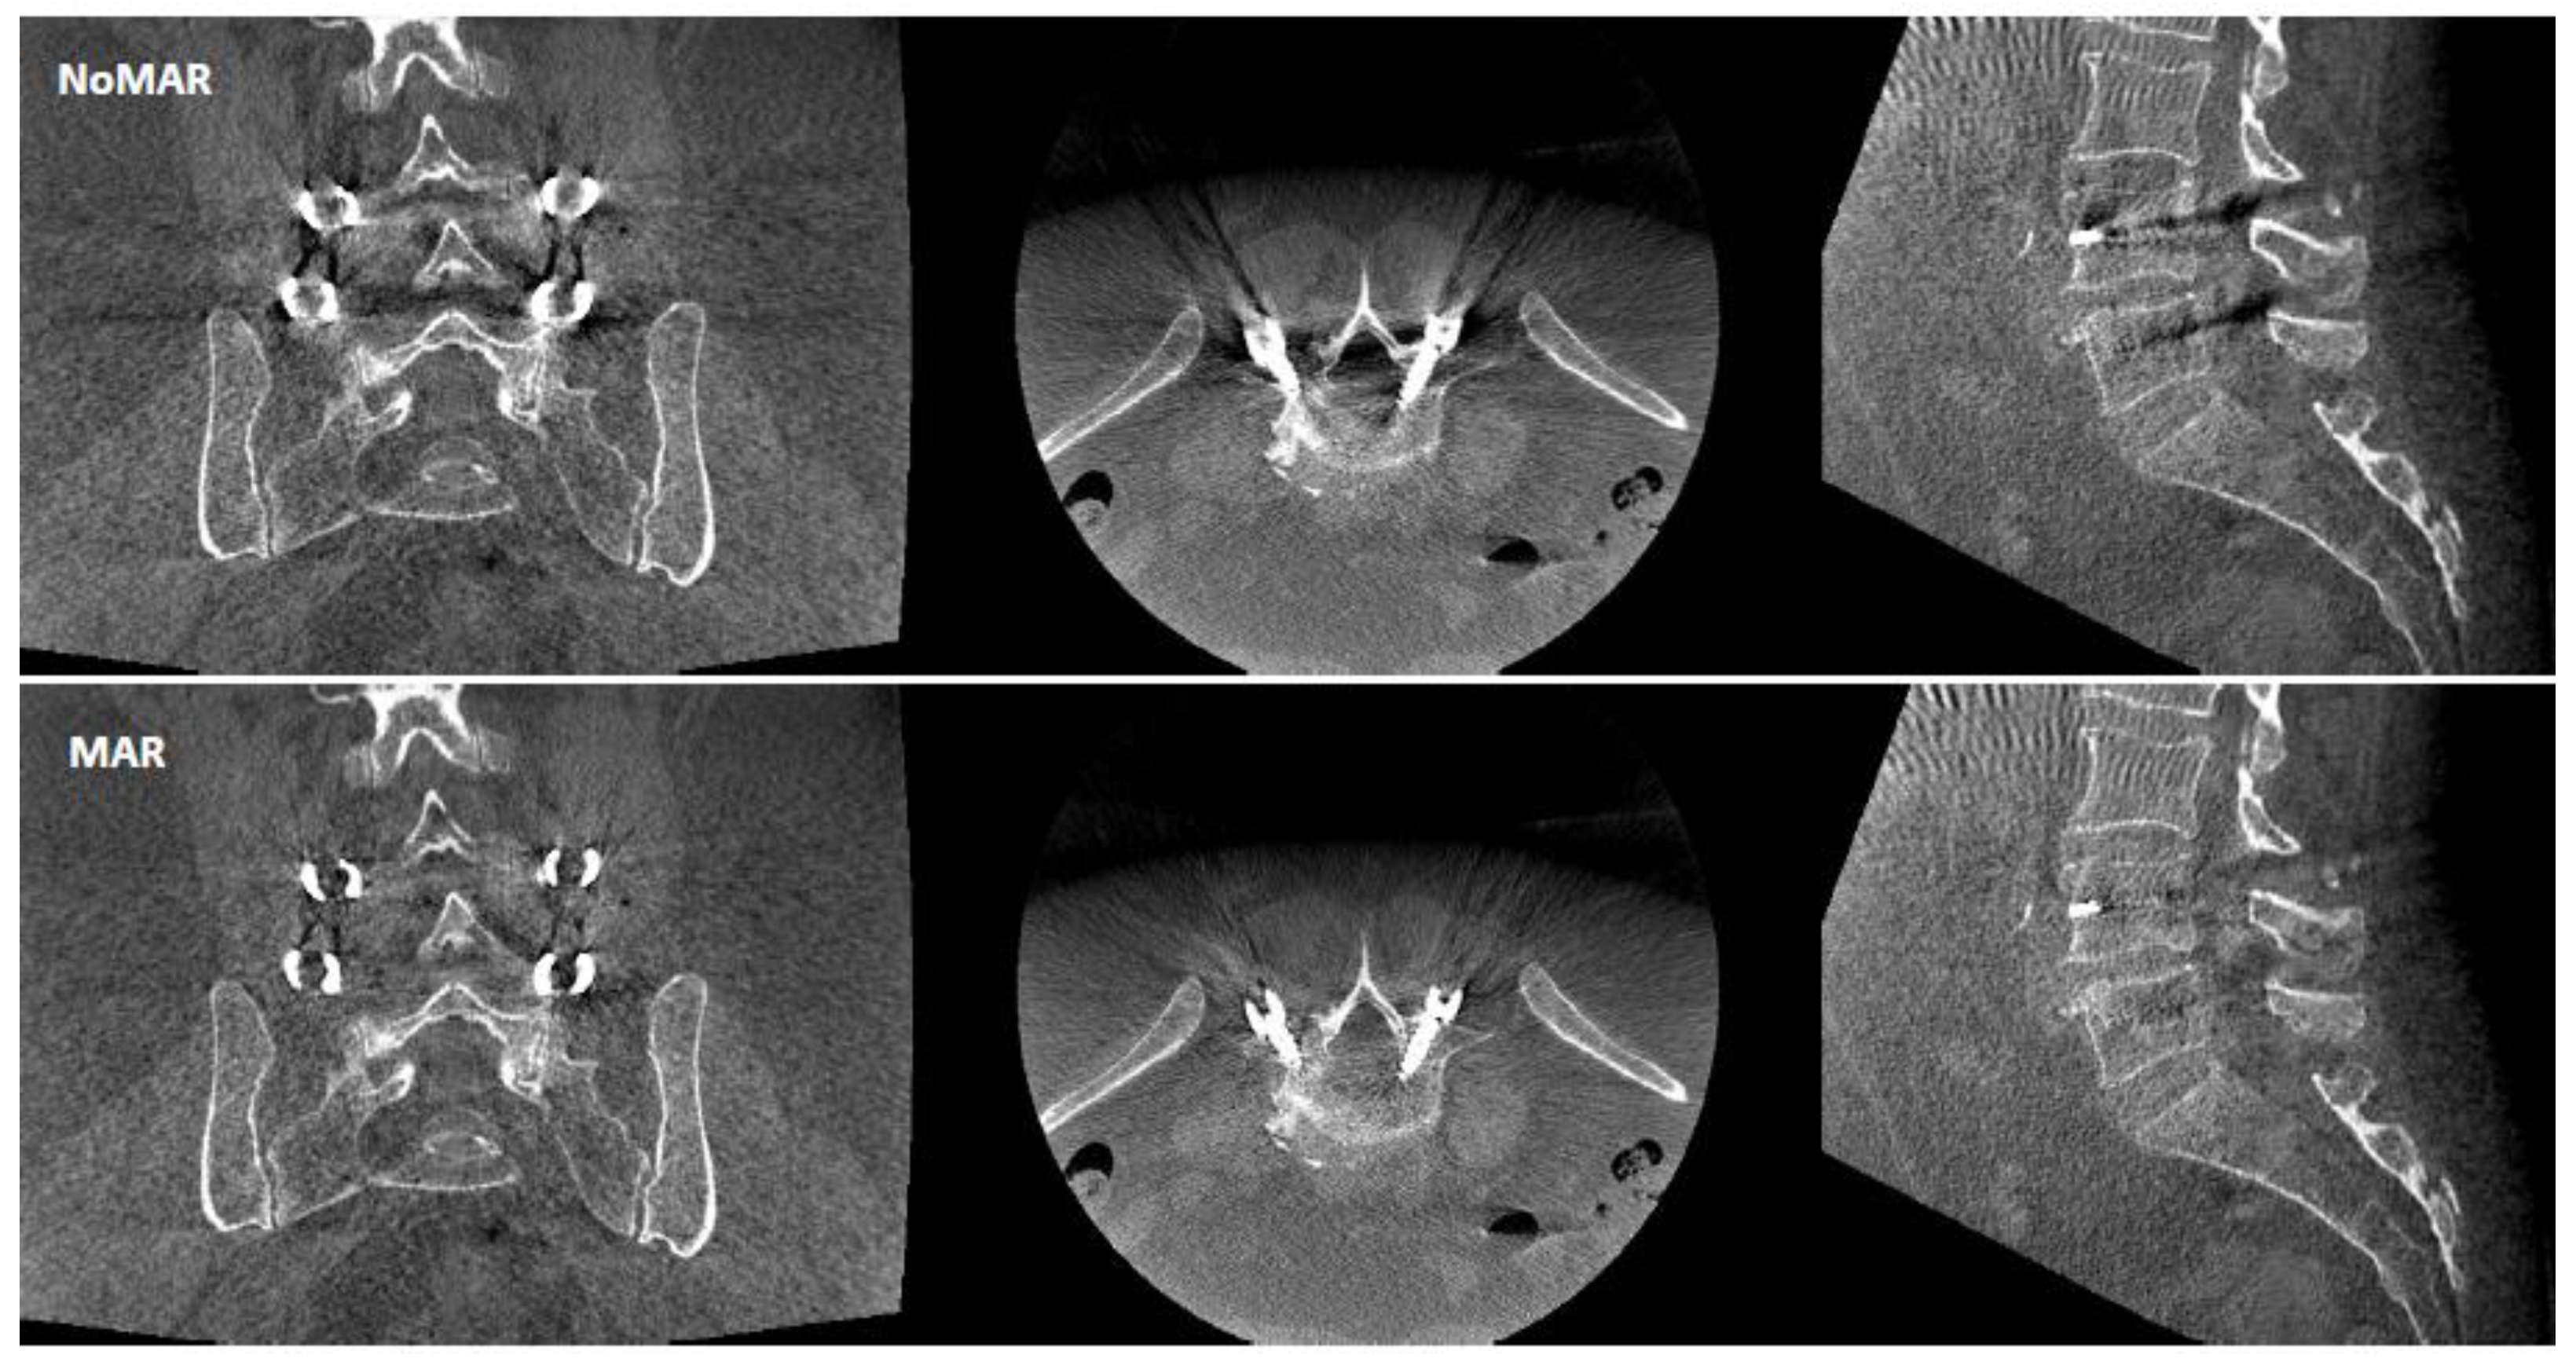

Figure 1.

Image quality for one patient using CBCT reconstruction without metal artifact reduction algorithm (NoMAR) and with metal artifact reduction algorithm (MAR) based on interpolation of projection data surrounding the metal shadow around the pedicle screws.